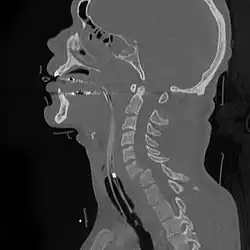

![]() | |

A fracture of the base of the dens (a part of C2) as seen on CT | |